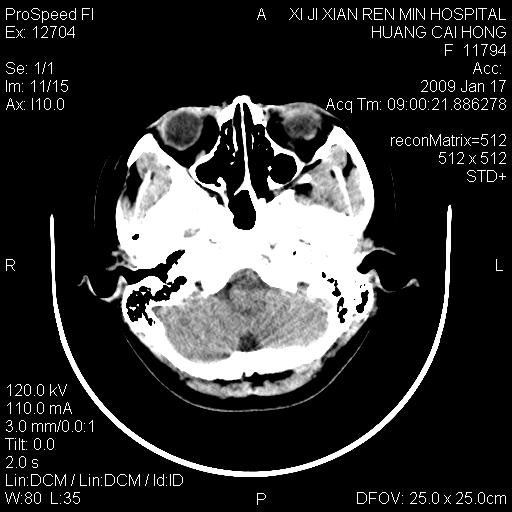

以下是引用zbp537在2009-1-19 13:54:00的发言:[br]首先考虑脑炎。[br]诊断依据:[br]1、患者较年轻。[br]2、有感冒病史。[br]3、左侧颞枕叶这么大一片低密度影,占位征象却不明显,不符合肿瘤特征,其内的高密度影为出血灶。

以下是引用xiaoniu在2009-1-19 13:29:00的发言:[br]左侧颞叶三角形低密度影,占位效应不明显,其内点片样高密都影,青少年患者,首先考虑:少突胶质瘤。因为有感冒病史,不能除外感染的可能。